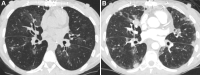

As lung transplantation has become the most effective definitive treatment option for end-stage chronic respiratory diseases, yearly rates of this surgery have been steadily increasing. Despite improvement in surgical techniques and medical management of transplant recipients, complications from lung transplantation are a major cause of morbidity and mortality. Some of these complications can be classified on the basis of the time they typically occur after lung transplantation, while others may occur at any time. Imaging studies, in conjunction with clinical and laboratory evaluation, are key components in diagnosing and monitoring these conditions. Therefore, radiologists play a critical role in recognizing and communicating findings suggestive of lung transplantation complications. A description of imaging features of the most common lung transplantation complications, including surgical, medical, immunologic, and infectious complications, as well as an update on their management, will be reviewed here. Keywords: Pulmonary, Thorax, Surgery, Transplantation Supplemental material is available for this article. © RSNA, 2021.